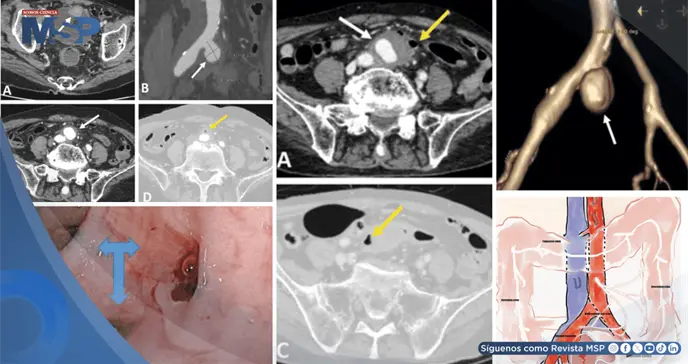

La tomografía computarizada identificó el crecimiento acelerado del aneurisma, gas perivascular e inflamación severa, hallazgos que permitieron diagnosticar una rara fístula entre la arteria ilíaca y el colon.

La situación clínica había empeorado considerablemente. Una nueva tomografía computarizada abdominal de urgencia mostró un cambio dramático: el aneurisma ilíaco había crecido de forma notable, alcanzando un tamaño de 31x36x40 milímetros, y ahora presentaba un trombo mural de 15 milímetros de espesor.

Los signos de inflamación y la presencia de gas en los tejidos circundantes también se habían incrementado de manera marcada.

El hallazgo radiológico más crítico fue la evidente adhesión de la pared anterior del aneurisma a la pared posterior del colon sigmoide. Para confirmar la sospecha, se realizó una colonoscopia, la cual mostró sangre fresca activa en esa misma zona del colon.

Con estas pruebas, se estableció el diagnóstico definitivo: una fístula aneurisma-colónica, una comunicación patológica entre el aneurisma infectado, denominado micótico, de la arteria ilíaca común derecha y la luz del colon sigmoide.

Sus hallazgos son determinantes: muestra el crecimiento del aneurisma, signos de infección activa como el edema y el gas en la grasa perivascular, y, de manera crítica, la relación anatómica entre el aneurisma y las estructuras digestivas adyacentes, sugiriendo la fístula. La presencia de gas extraintestinal o la extravasación de medio de contraste hacia la luz del colon son hallazgos altamente específicos.